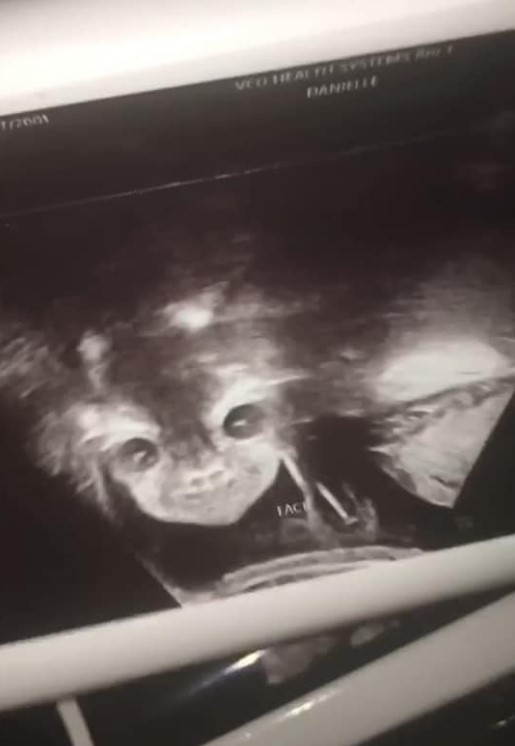

Con 24 semanas de gestación, a Iyanna le confirmaron que tendrá una nena, pero reaccionó con sorpresa al ver la carita de su hija, que según ella se parece "a la del diablo".

Lo que realmente pasó es que la nena apareció de frente en el ultrasonido, algo poco habitual ya que suelen estar de costado y pro eso la imagen se distorsionó un poco, haciéndola parecer a un demonio.

my weird ass daughter bra most babies hide from the camera look at her demon mfn ass bra♀️♀️♀️♀️ she…